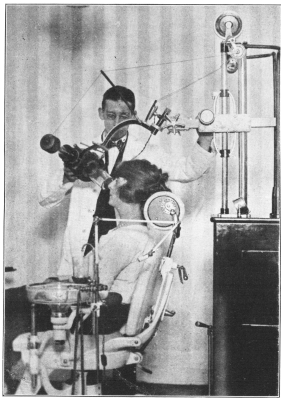

X-Raying the Teeth and Jaw—Health Often Depends on Their Good Condition | 224 |

Throat Examination—Important in Determining Physical Condition | 225 |